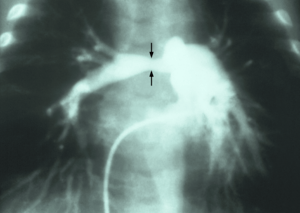

Stenosis of pulmonary artery

| Stenosis of the right pulmonary artery in a patient which was due to a case of congenital rubella. | |

Stenosis of the pulmonary artery is a condition where the pulmonary artery is subject to an abnormal constriction (or stenosis).[1] Peripheral pulmonary artery stenosis may occur as an isolated event or in association with Alagille syndrome, Berardinelli-Seip congenital lipodystrophy type 1, Costello syndrome, Keutel syndrome, nasodigitoacoustic syndrome (Keipert syndrome), Noonan syndrome or Williams syndrome.